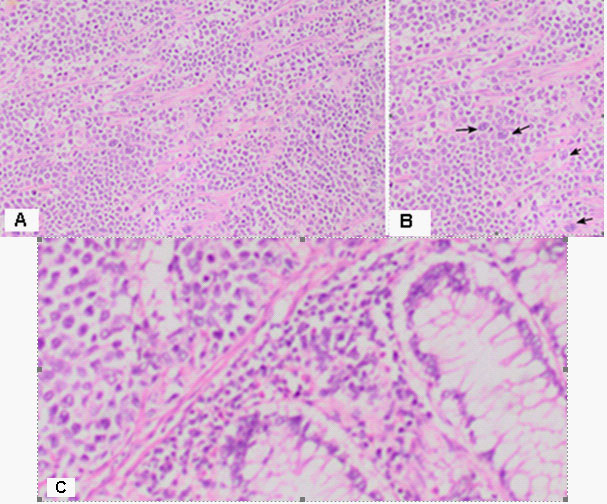

The result of a histological findings - Macroscopic

Part of a thick intestine with a size of 30 cm with a omentum. In the middle part of the resectеd colon, there is a tumor formation with a diameter of 10 cm. Eccentrically encompassing the intestine along the 10 cm. The tumor has a whitish color and macroscopically resembles fish meat. Seven lymph nodes were removed. Microscopic -Part of a thick intestine with a tumor histologically represented by diffuse cultivated tumor cells with scarce cytoplasm, circular polymorphic nuclei with visible nucleoli and high mitotic activity / over 10 mitoses per 10 high-power fields. The wall of colon with massive, diffuseinfiltration from large and medium-sized neoplastic cells. They have a slightly pronounced polymorphism, a dischositive way of growth, some of them with vesicular nuclei and prominent nucleoli (Figure 3A,C). Well taken out Reed-Sternberg like cells (Figure 3B). There are extensive zones with epithelium atrophy. The tumor infiltrates mucose, submucosa, smooth muscle layer, subset fat and serosis (Figure 4A). Morphology is a characteristic of MALT lymphoma. In three of the surveyed seven lymph nodes, a diffuse deletion structure was established due to tumor infiltration (Figure 4B). The resection lines are clean, without tumor infiltration. To establish the type of lymphoma, Immunohistochemical (IHC) analysis is imposed.

Figure 3: Microscopic histological findings: (A) The tumor histologically represented by diffuse cultivated tumor cells with scarce cytoplasm, circular polymorphic nuclei with visible nucleoli and high mitotic activity / over 10 mitoses per 10 high-power fields H&E, x20. (B) Well taken out Reed-Sternberg like cells (mentioned with black arrow) H&E, x20. (C) The wall of colon with massive, diffuse infiltration from large and medium-sized neoplastic cells. They have a slightly pronounced polymorphism, a dischositive way of growth, some of them with vesicular nuclei and prominent nucleoli H&E, x200.

DLBCL is neoplasm of large B lymphoid cells with nuclei at least 2× size of lymphocyte [20]. The pathomorphological characteristic is expressed by diffuse growth pattern with large cells (usually 5× normal lymphocytes) resembling immunoblasts (amphophilic cytoplasm, eccentric nuclei with one central nucleoli) or centroblasts (pale or basophilic cytoplasm, vesicular chromatin due to chromatin margination, 2 - 3 nucleoli, often near membrane), or rarely, anaplastic, associated with neutrophils [21]. In Figure 3 we present diffuse tumor cells with scarce cytoplasm, circular polymorphic nuclei with visible nucleoli and high mitotic activity / over 10 mitoses per 10 high-power fields. In Figure 4A is clearly seen the wall of colon with massive, diffuse infiltration from large and medium-sized neoplastic cells with slightly pronounced polymorphism, a dischositive way of growth, some of them with vesicular nuclei and prominent nucleoli. In three of the surveyed seven lymph nodes, a diffuse deletion structure was established due to tumor infiltration (Figure 4B).